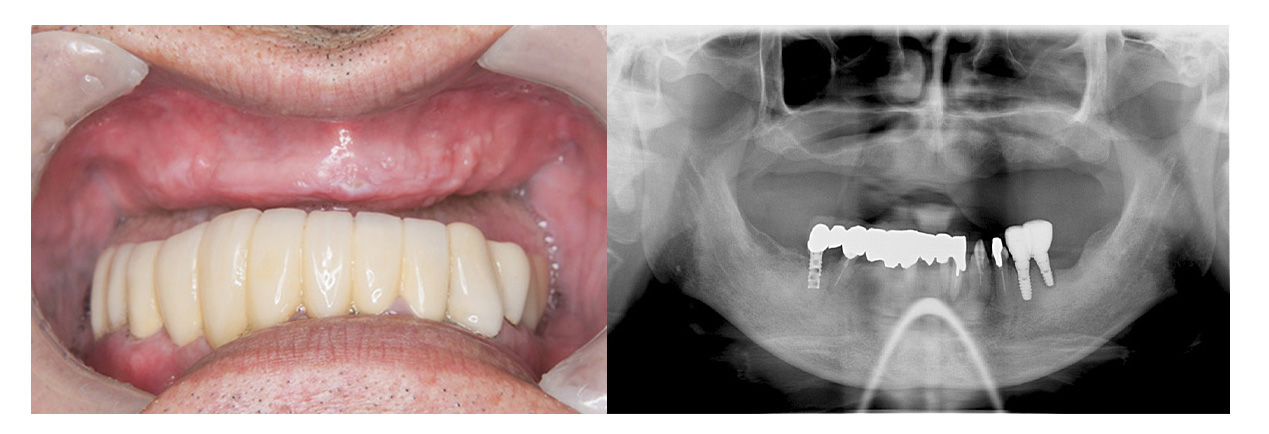

症例写真の紹介

ここで、当院がこれまでに治療してきたオールオン4やザイゴマの症例写真をご覧ください。お口の状況がどれほど改善されるかがイメージしやすくなるかと思います。

症例④オールオン4

• Before

• After

咀嚼、審美障害。歯周病でグラグラな歯を全部抜歯してオールオン4で治療した症例。